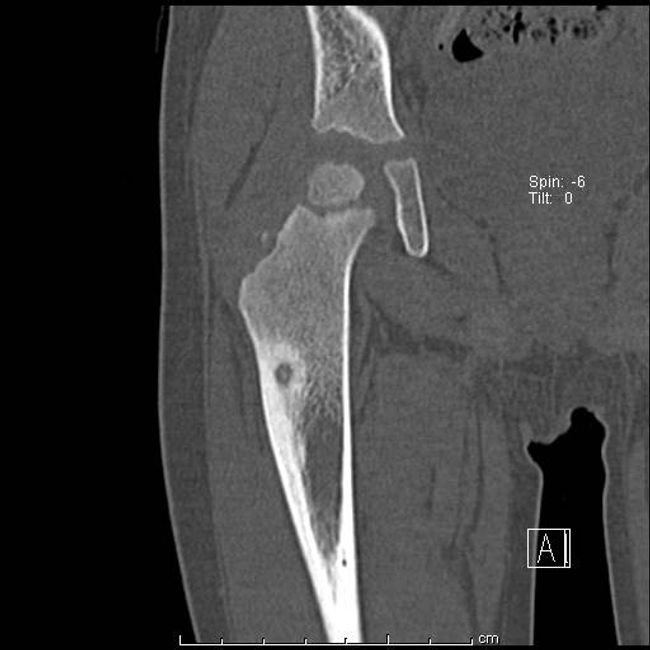

Костная киста большеберцовой 143 фотографий